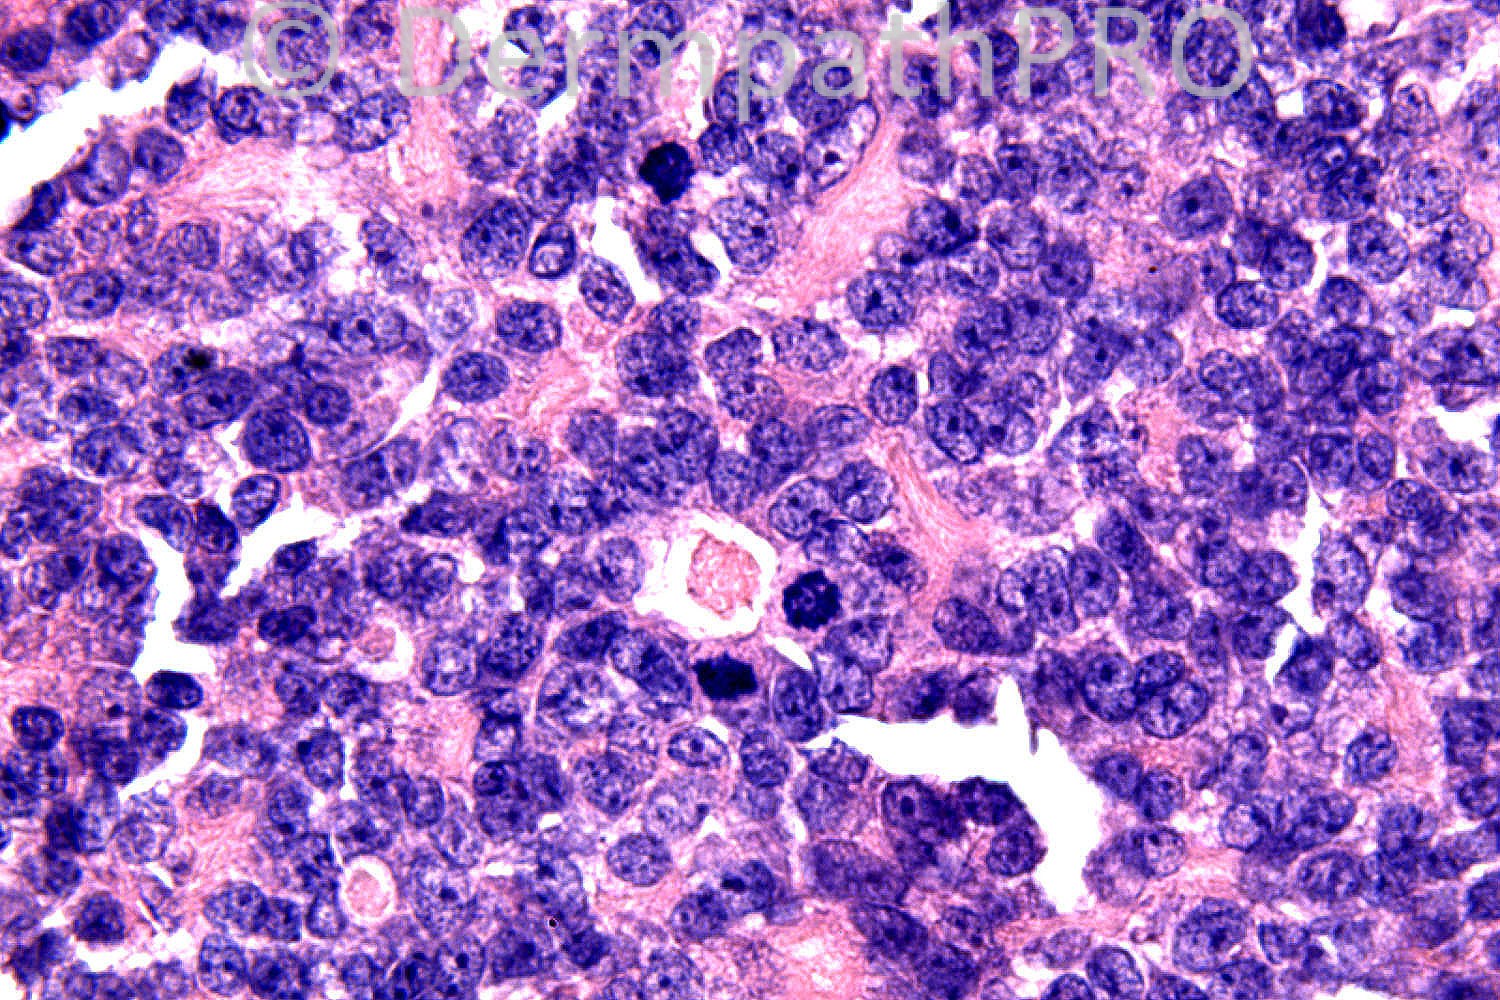

54 years-old male. Scalp. Tumour at vertex. ?Appendageal.